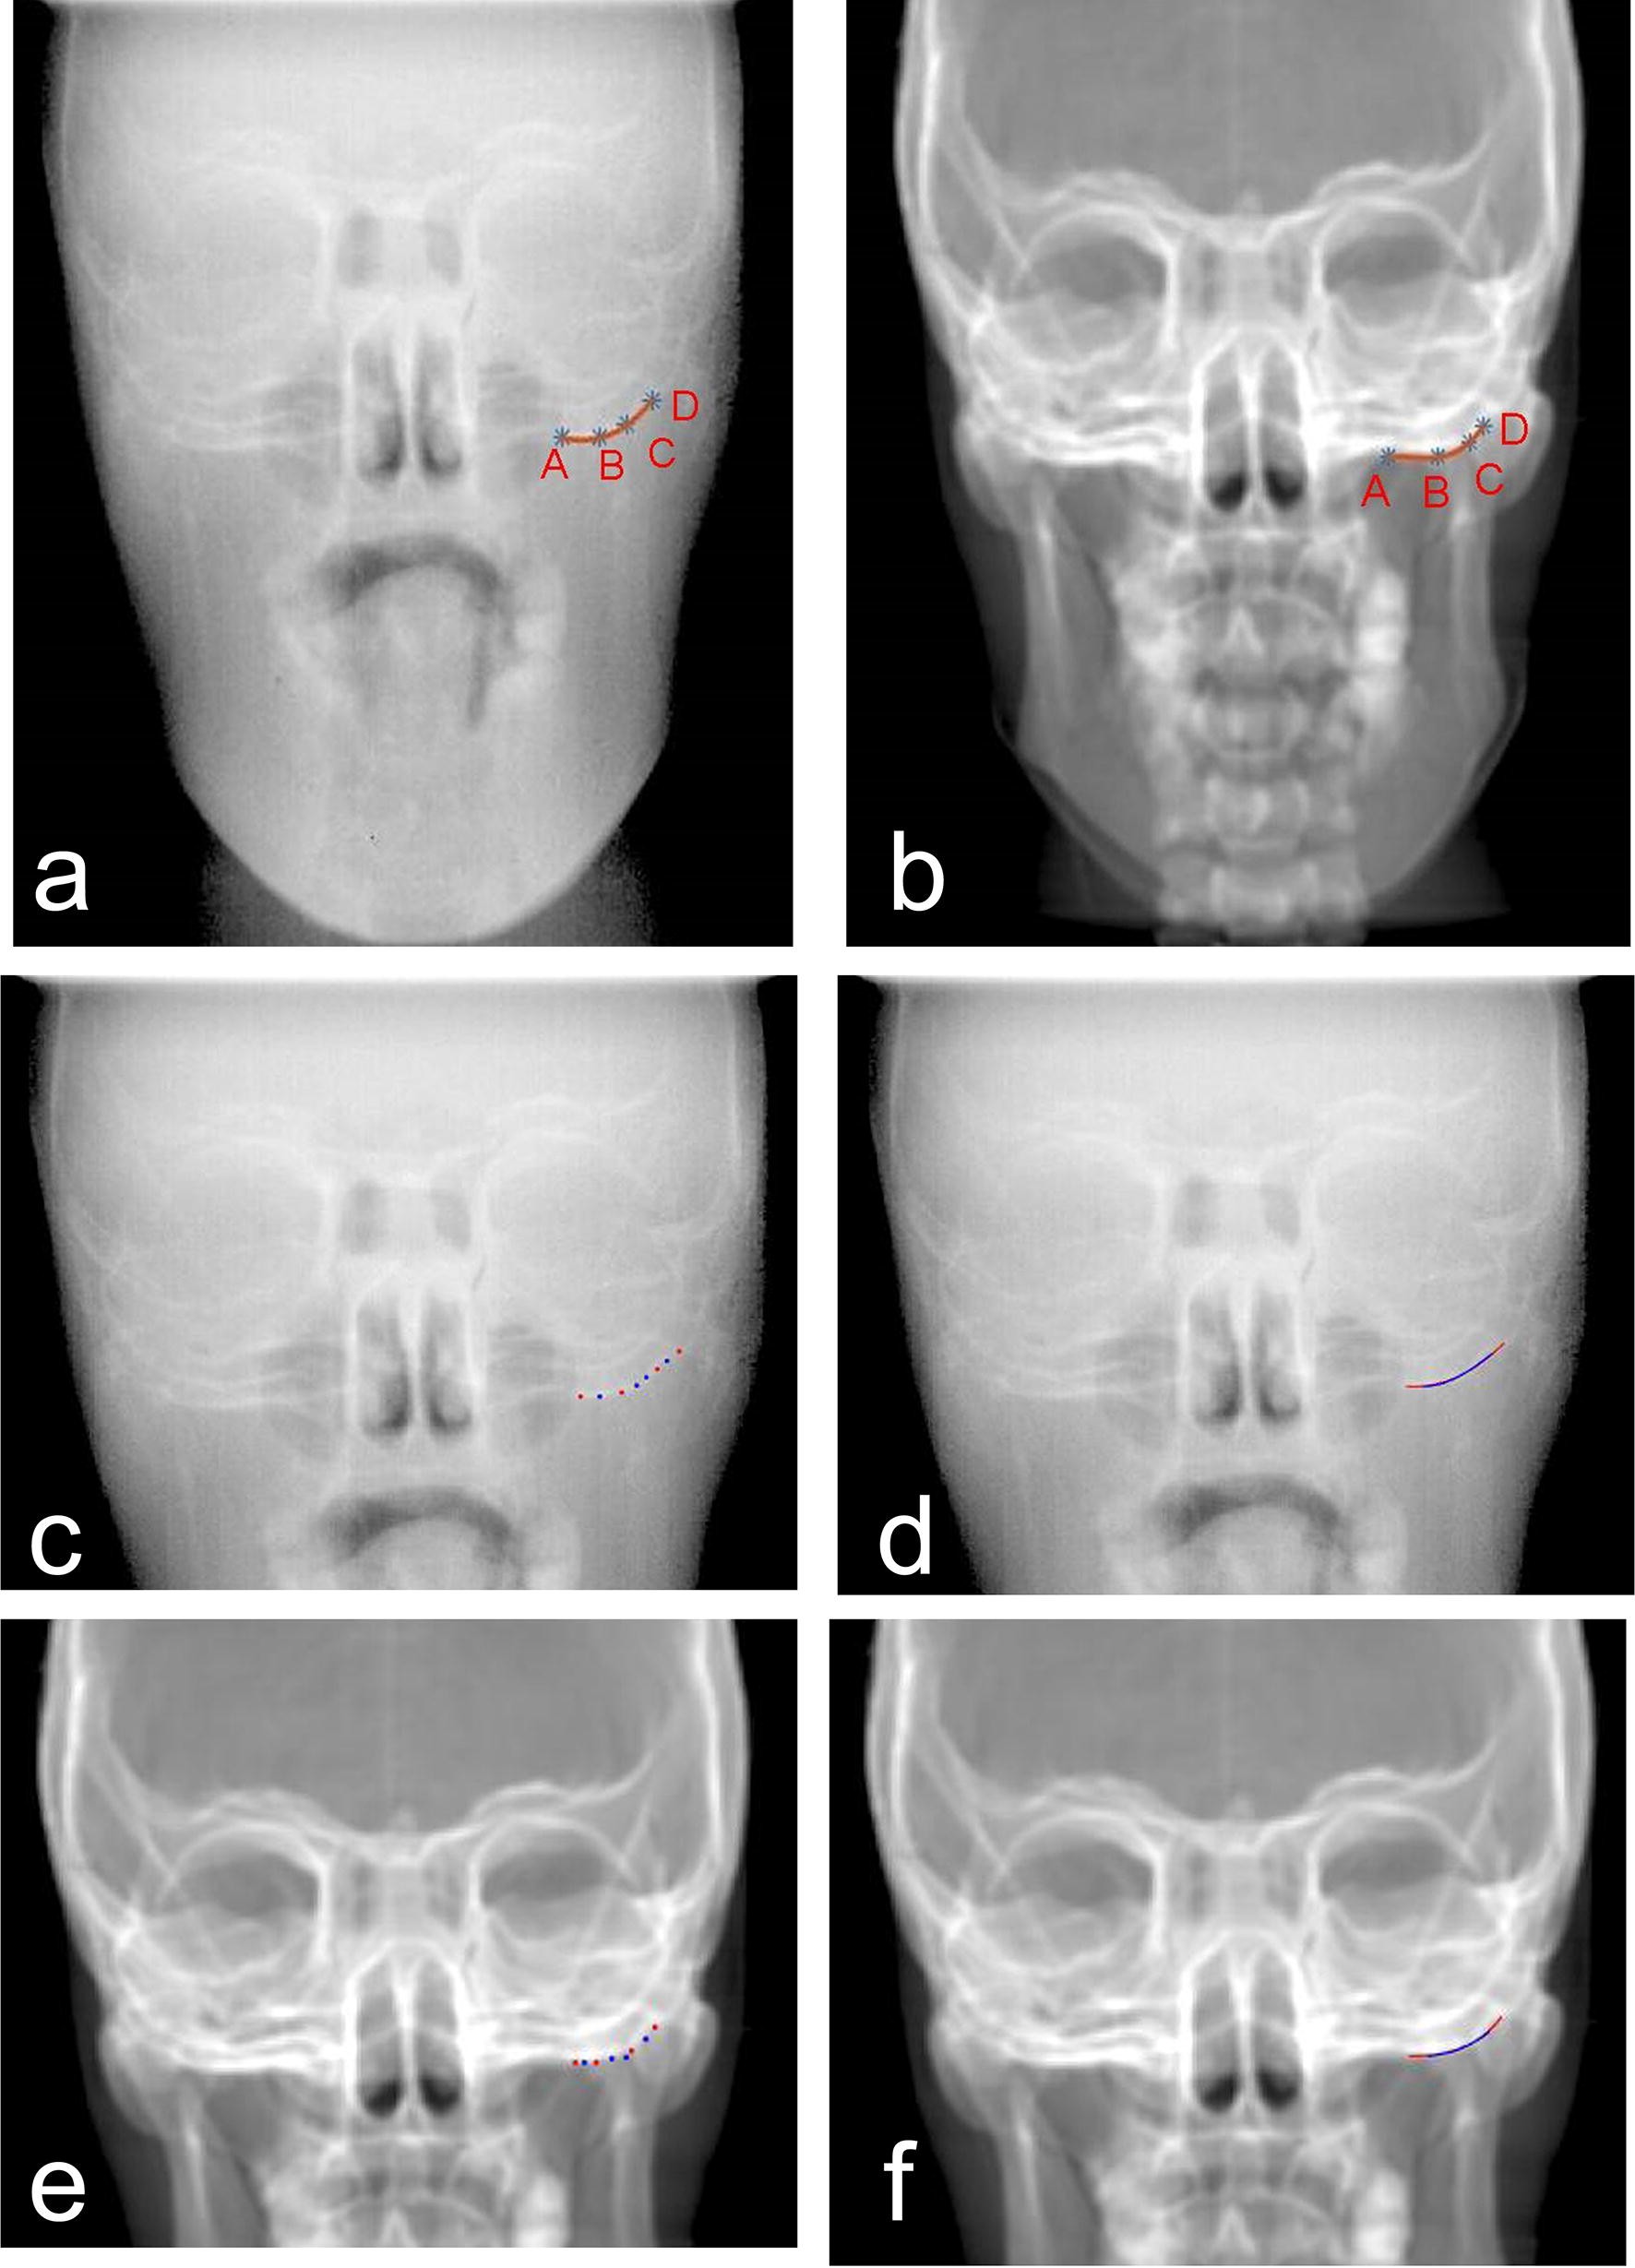

Figure 1

Cubic polynomial curve fitting basing on four markers. Cubic polynomial curve fitting from EPID (a) and DRR (b) images of the same phantom in the same position. Repeated cubic polynomial curve fittings from the EPID images of the same phantom in the same position based on two different groups four markers in EPID and DRR images (Eight different points in (c) for the EPID image and (e) for DRR image, red and blue curves in (d) for the EPID image and (e) for DRR image).